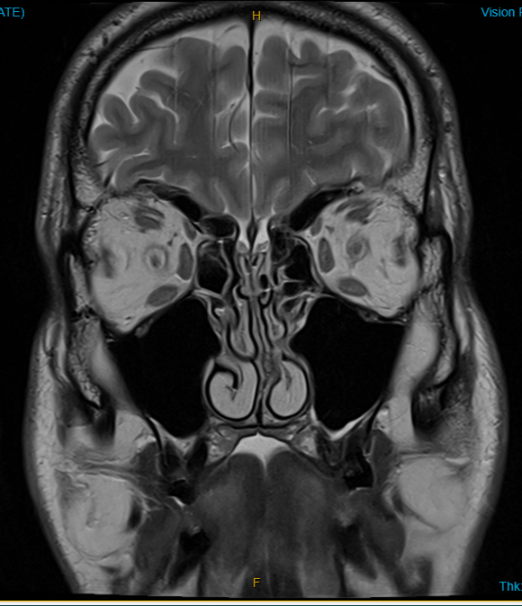

MRI brain and orbits x 5 normal. 2017 2018 2018 2024 2025: prominence of the left optic nerve sheath

7Jan25 MRI – Hypoplasia of the left transverse sigmoid sinus with possible narrowing at the right sigmoid transverse junction. Flattening of the posterior sclera right >left . Has moderate fluid within the optic nerve sheath,.